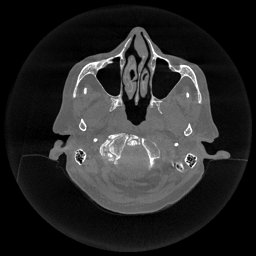

The results for simulated noisy data are shown in Fig. 2. The first and third rows display two representative slices from the test set, and the second and fourth rows present the corresponding error maps. The traditional WCE method suppresses cupping artifacts and recovers some missing anatomical structures but still shows noticeable deviations from the ground truth. Predictions from the four diffusion-based models demonstrate a markedly improved ability to restore anatomical structures. Among them, cDDPM fails to fully reconstruct the patient bed and retains residual noise in its outputs. This noise is attributable to an incomplete reverse denoising process rather than residual Poisson noise, as evidenced in our noise-free experiments (Fig. 5 in the Appendix). PatchDiffusion, diffusionGAN, and I2SB achieve similar visual quality, with I2SB producing the cleanest and most consistent reconstructions.

Quantitative results in Tab. V further confirm I2SB’s superiority over conventional deep learning methods such as FBPConvNet and Pix2pixGAN across RMSE, PSNR, and SSIM. Compared to other diffusion models—including cDDPM, PatchDiffusion, and cLDM—I2SB delivers higher image quality, while diffusionGAN achieves comparable quantitative performance. However, I2SB demonstrates a significant advantage in inference efficiency, as summarized in Tab. IV.

III-D Real Clinical Data Experiment

The experimental results on clinical head data are shown in Fig. 4. The reference images were reconstructed using the fast iterative shrinkage-thresholding algorithm (FISTA) with total variation regularization from non-truncated projection data. In the WCE reconstructions (Fig. 4(b)), severe truncation prevents accurate recovery of anatomical structures outside the FOV. Despite being trained solely on simulated data with a domain gap, all deep learning models can restore a substantial portion of the missing anatomy. Among them, the diffusion-based methods recover soft-tissue boundaries more faithfully than the conventional deep learning approach FBPConvNet, highlighting their stronger image generation capability. However, cDDPM reconstructions exhibit more noticeable noise than those from other methods, consistent with the simulated data results. The patchDiffusion model introduces artifacts within the FOV, likely due to its patch-wise processing strategy. While I2SB shares the same limitations as other diffusion models in perfectly restoring soft-tissue detail, it produces fewer residual noise patterns and fewer artifacts within the FOV boundaries. Overall, Fig. 4 demonstrates the strong efficacy of I2SB in reconstructing real CBCT data.